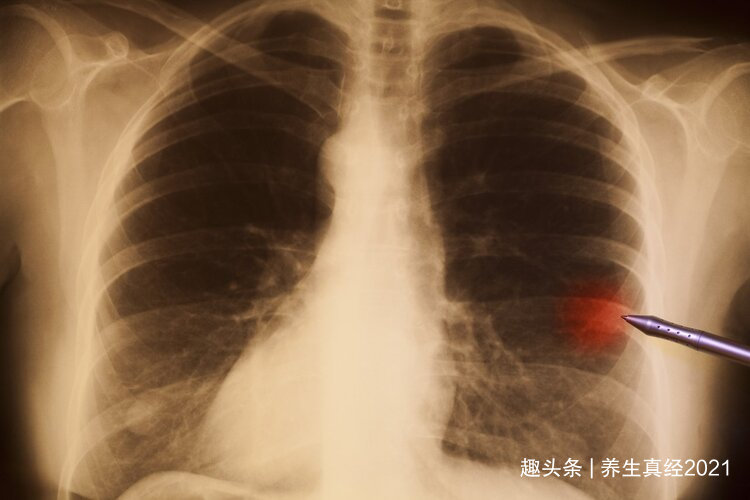

近日,江苏杨女士体检发现肺部出现“5mm小阴影”,由于结节太小无法辨认良恶性质,医生建议定期复查。然而,李女士却把这个结节当成了“定时炸弹”,为此忧心忡忡、没有胃口,一个月就瘦了八斤。

在丈夫的陪同下,李女士到市肿瘤医院详细检查,王宇峰教授通过穿刺活检,确认李女士的小结节是原位腺部肿瘤,虽然是恶性早期肿瘤,但经过微创消融技术处理后,只要定期复查即可。

很多人发现肺结节都和李女士一样紧张焦虑,但肺部有结节就等于患有恶性肿瘤吗?非也,体检结果不能100%说明情况,我们应该正确认识体检报告!

肺结节是非常常见的一种肺部疾病,很多人把肺结节当成肺癌,其实是错误的理解。

淮安市第一人民医院肿瘤内科喻晓娟副主任表示,肺部结节实际上是肺部的小型肿块,可能是肺部感染、长期处于污染严重的地区等因素造成的。肺部结节<2cm多为良性,即使检查出肺结节也不一定会发展成肺癌,通常前期加以控制,必要时进行治疗,是能够恢复的。

所以,肺结节不能和肺癌直接挂钩,检查出肺结节也不要太慌张。

深圳78岁的李大爷去年年底咳嗽不止,还以为是感冒,直到病情越发严重才前往中山七院检查,通过肺部CT确诊肺癌,且已经出现了转移。李大爷和家人不敢置信,李大爷每年都会做胸部X光检查,为何一直都没有查出肺癌呢?

事实上,X光早期肺癌检出率仅为0-15%,用X光片筛查肺癌完全是“假装防癌”。大家在选择体检项目时,也要注意有三个检查是没有必要做的!

肺部和心脏、纵隔等组织重叠,即使癌变,X光也无法早期筛查出来,就算查出来了,也可能已经是肺癌中晚期。一般肺癌筛查手段还是以低剂量螺旋CT为主,与X光相比,它射线量低、分辨率较高,能帮助患者发现早期肺癌。